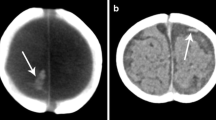

Lollipop sign in a 31-month-old boy who presented with tibial metaphyseal fracture, multiple vertebral compression fractures, bilateral subdural hemorrhage, retinal hemorrhage and diffuse hypoxic–ischemic injury of the brain. Brain MRI demonstrates lollipop sign (arrows) overlying the left cerebral convexity, which is (a) hypointense with blooming on axial T2* gradient recalled echo sequence. b, c CT venogram confirms terminal hyperattenuation on (b) unenhanced image and lack of intraluminal contrast on (c) post-contrast CT in the cortical bridging vein in question, which terminates abruptly

Lollipop and compression signs in a 2-month-old boy with multiple extremity and rib fractures. a Coronal MP-RAGE MR sequence demonstrates large subdural hemorrhage bilaterally (arrows). b Axial T2* gradient recalled echo sequence shows lollipop sign with a torn bridging vein terminating in a clot with terminal thrombosis, demonstrating blooming (arrow) with bilateral subdural hemorrhage (arrowheads). c Reconstructed MR venography sequence demonstrates paucity of cortical bridging veins draining into the superior sagittal sinus superiorly, consistent with compression. MP-RAGE magnetization-prepared rapid gradient echo imaging